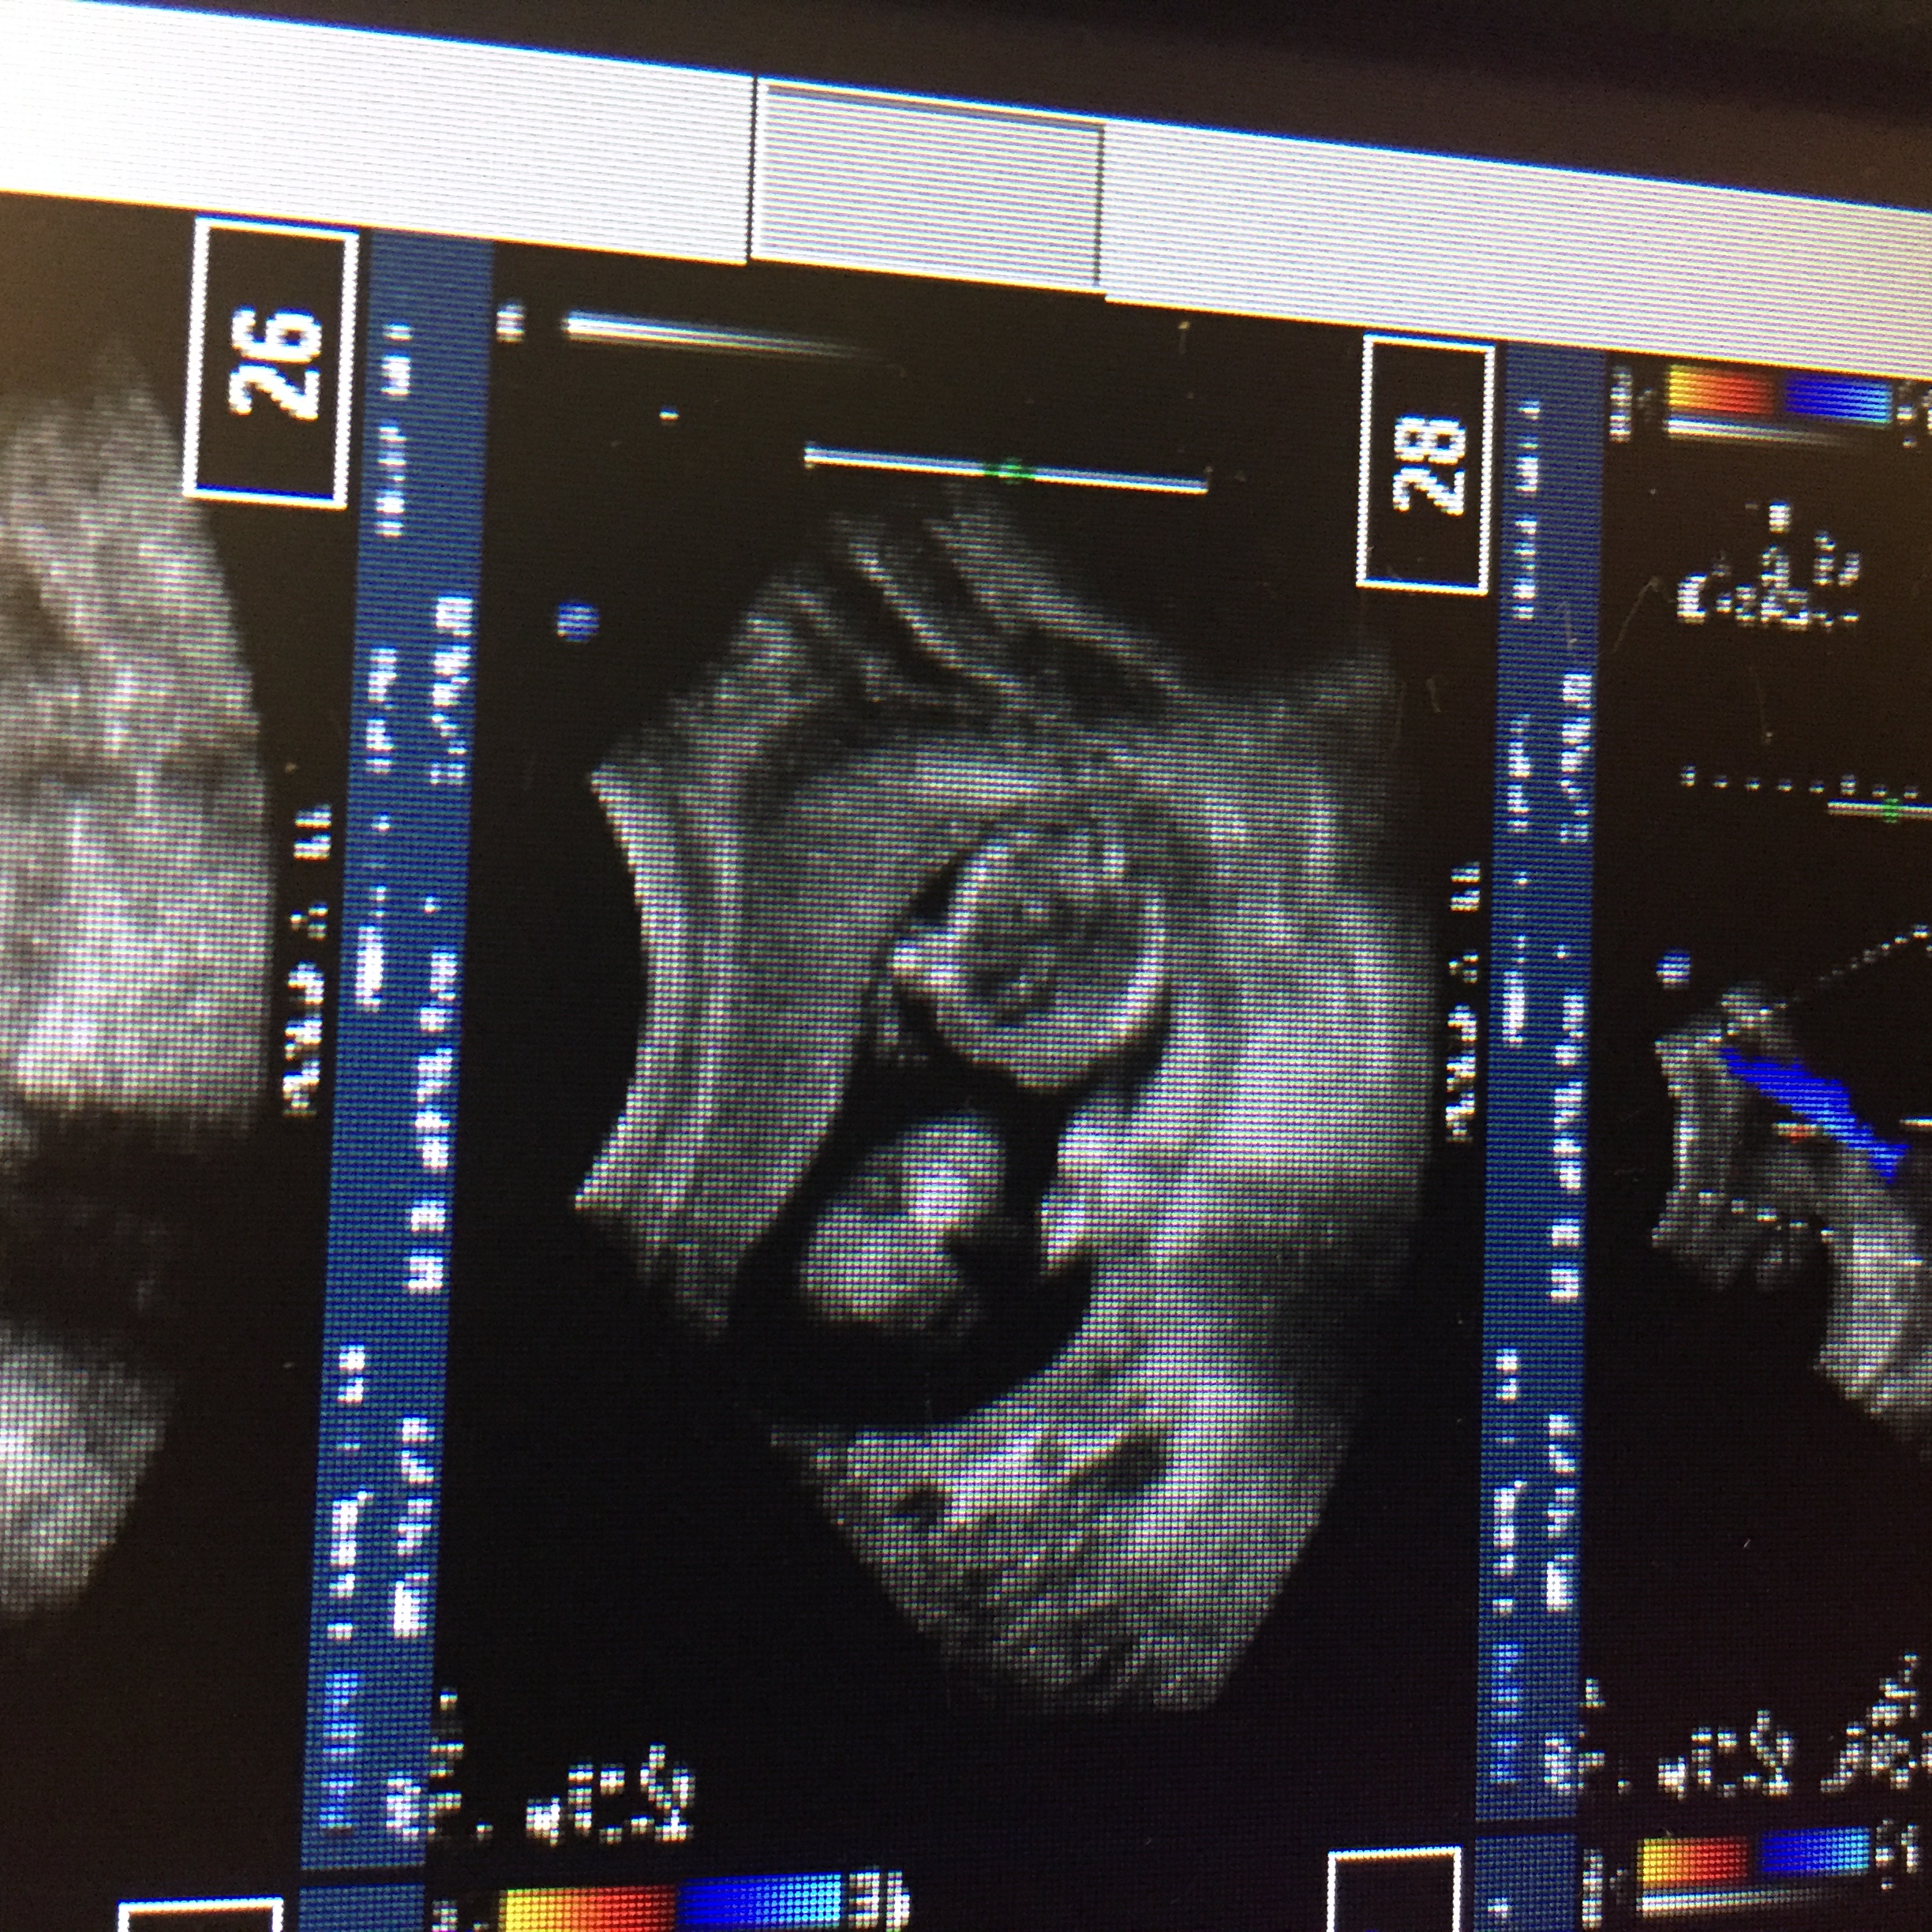

These are from 16 weeks as well. Can you see anything from the front?

Attachment 33126

Attachment 33127